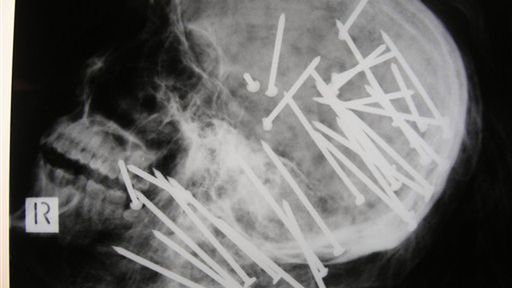

Szokujące zdjęcie: 34 gwoździe w głowie ofiary

Australijska policja ujawniła szokujące zdjęcie rentgenowskie, które przedstawia czaszkę chińskiego imigranta zamordowanego za pomocą 34 wbitych w głowę ogromnych gwoździ - podaje Reuters.

Jak twierdzi policja, 27-letni Chen Liu zginął z pistoletu powszechnie dostępnego i szeroko używanego w budownictwie, służącego do wbijania 8,5-centymetrowych gwoździ.

Chińczyk przybył do Australii w 2000 roku, rok temu bliscy zgłosili jego zaginięcie. Niedługo potem dzieci znalazły zwłoki mężczyzny na położonych na południe od Sydney bagnach. Ciało było zawinięte w dywan i związane drutem.